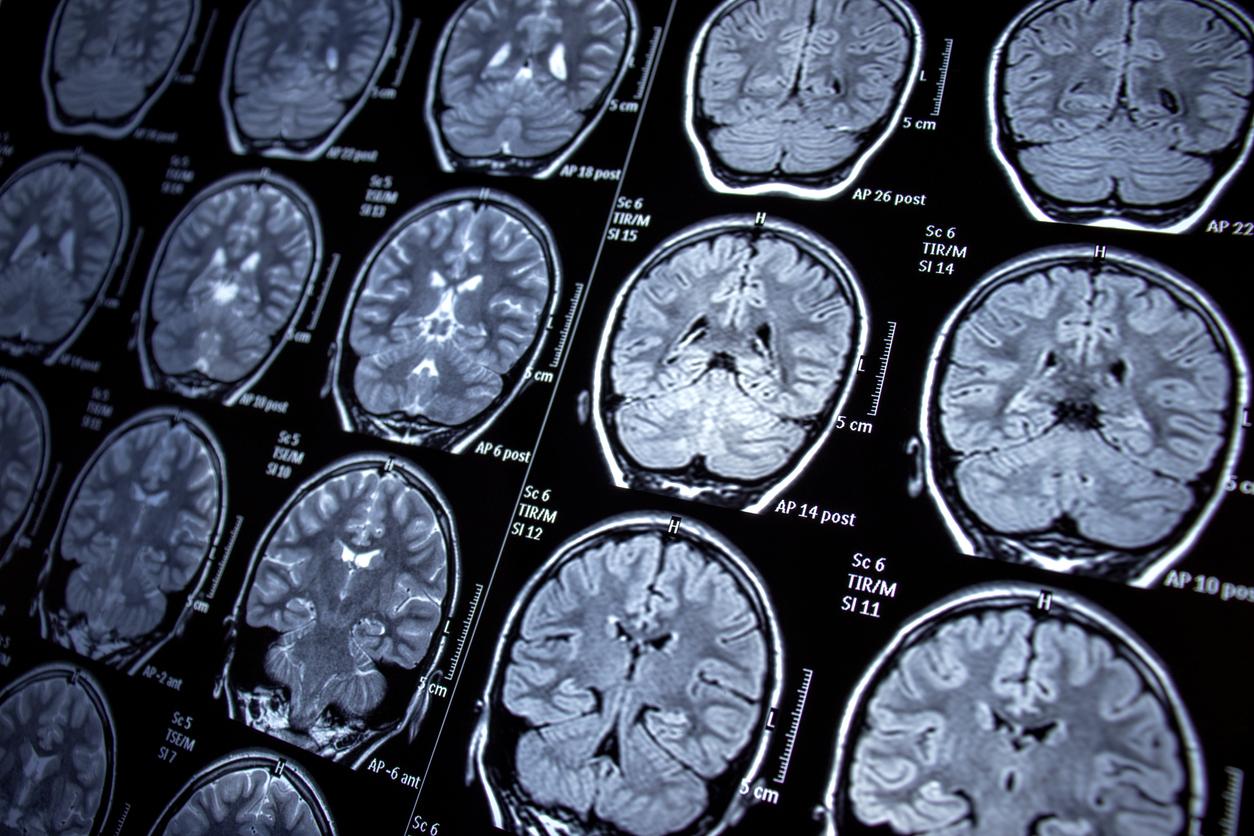

Diminution des fonctions cognitives, troubles de la mémoire, de l'exécution de gestes simples, de l'orientation dans le temps et l'espace… Ces symptômes de la maladie d’Alzheimer sont dus à la dégénérescence des neurones liée à la formation de plaques amyloïdes. Ces dernières empêchent, entre autres, les neurones de bien fonctionner. Actuellement, il n’existe pas de traitement curatif pour cette pathologie. Cependant, des chercheurs ont peut-être trouvé une nouvelle piste.

Dans une étude publiée dans la revue Cell, les scientifiques expliquent que la stimulation cérébrale des nouveaux neurones, ceux qui sont produits à l’âge adulte dans l’hippocampe, pourrait aider à restaurer les fonctions cognitives réduites par la maladie. C’est du moins ce qu’ils ont observé lors de leurs essais cliniques sur des souris.

La neurogenèse est la création de nouveaux neurones dans l’hippocampe, une région du cerveau très impliquée dans l'apprentissage et la mémoire. C’est ce phénomène que les scientifiques ont étudié. “Nous avons été surpris de constater que l'activation d'une petite population de nouveaux neurones nés à l'âge adulte était suffisante pour [améliorer significativement] les fonctions cérébrales”, explique Juan Song, auteur principal de l’étude.

Pour activer les neurones et stimuler le noyau suprammamillaire (SuM) situé dans l’hippocampe, les chercheurs ont utilisé une technique de stimulation cérébrale profonde appelée optogénétique. Selon l'Institut national de la santé et de la recherche médicale (Inserm), elle consiste à “introduire dans une cellule un gène qui code pour une protéine photosensible, laquelle va s'activer lorsqu'on l'éclaire avec une lumière spécifique.” Ainsi, ils l'ont utilisé pour stimuler le SuM et améliorer la neurogenèse hippocampique adulte (AHN) chez des souris atteintes de la maladie d'Alzheimer.